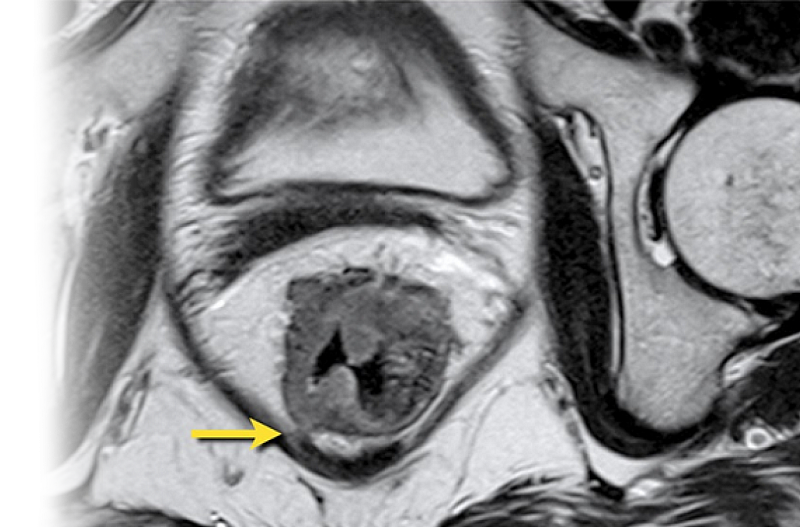

Магнитно-резонансная томография анального канала с контрастом (при парапроктитах и свищах) – важный метод исследования с применением контрастного вещества, который позволяет визуализировать анальный канал и окружающие структуры.